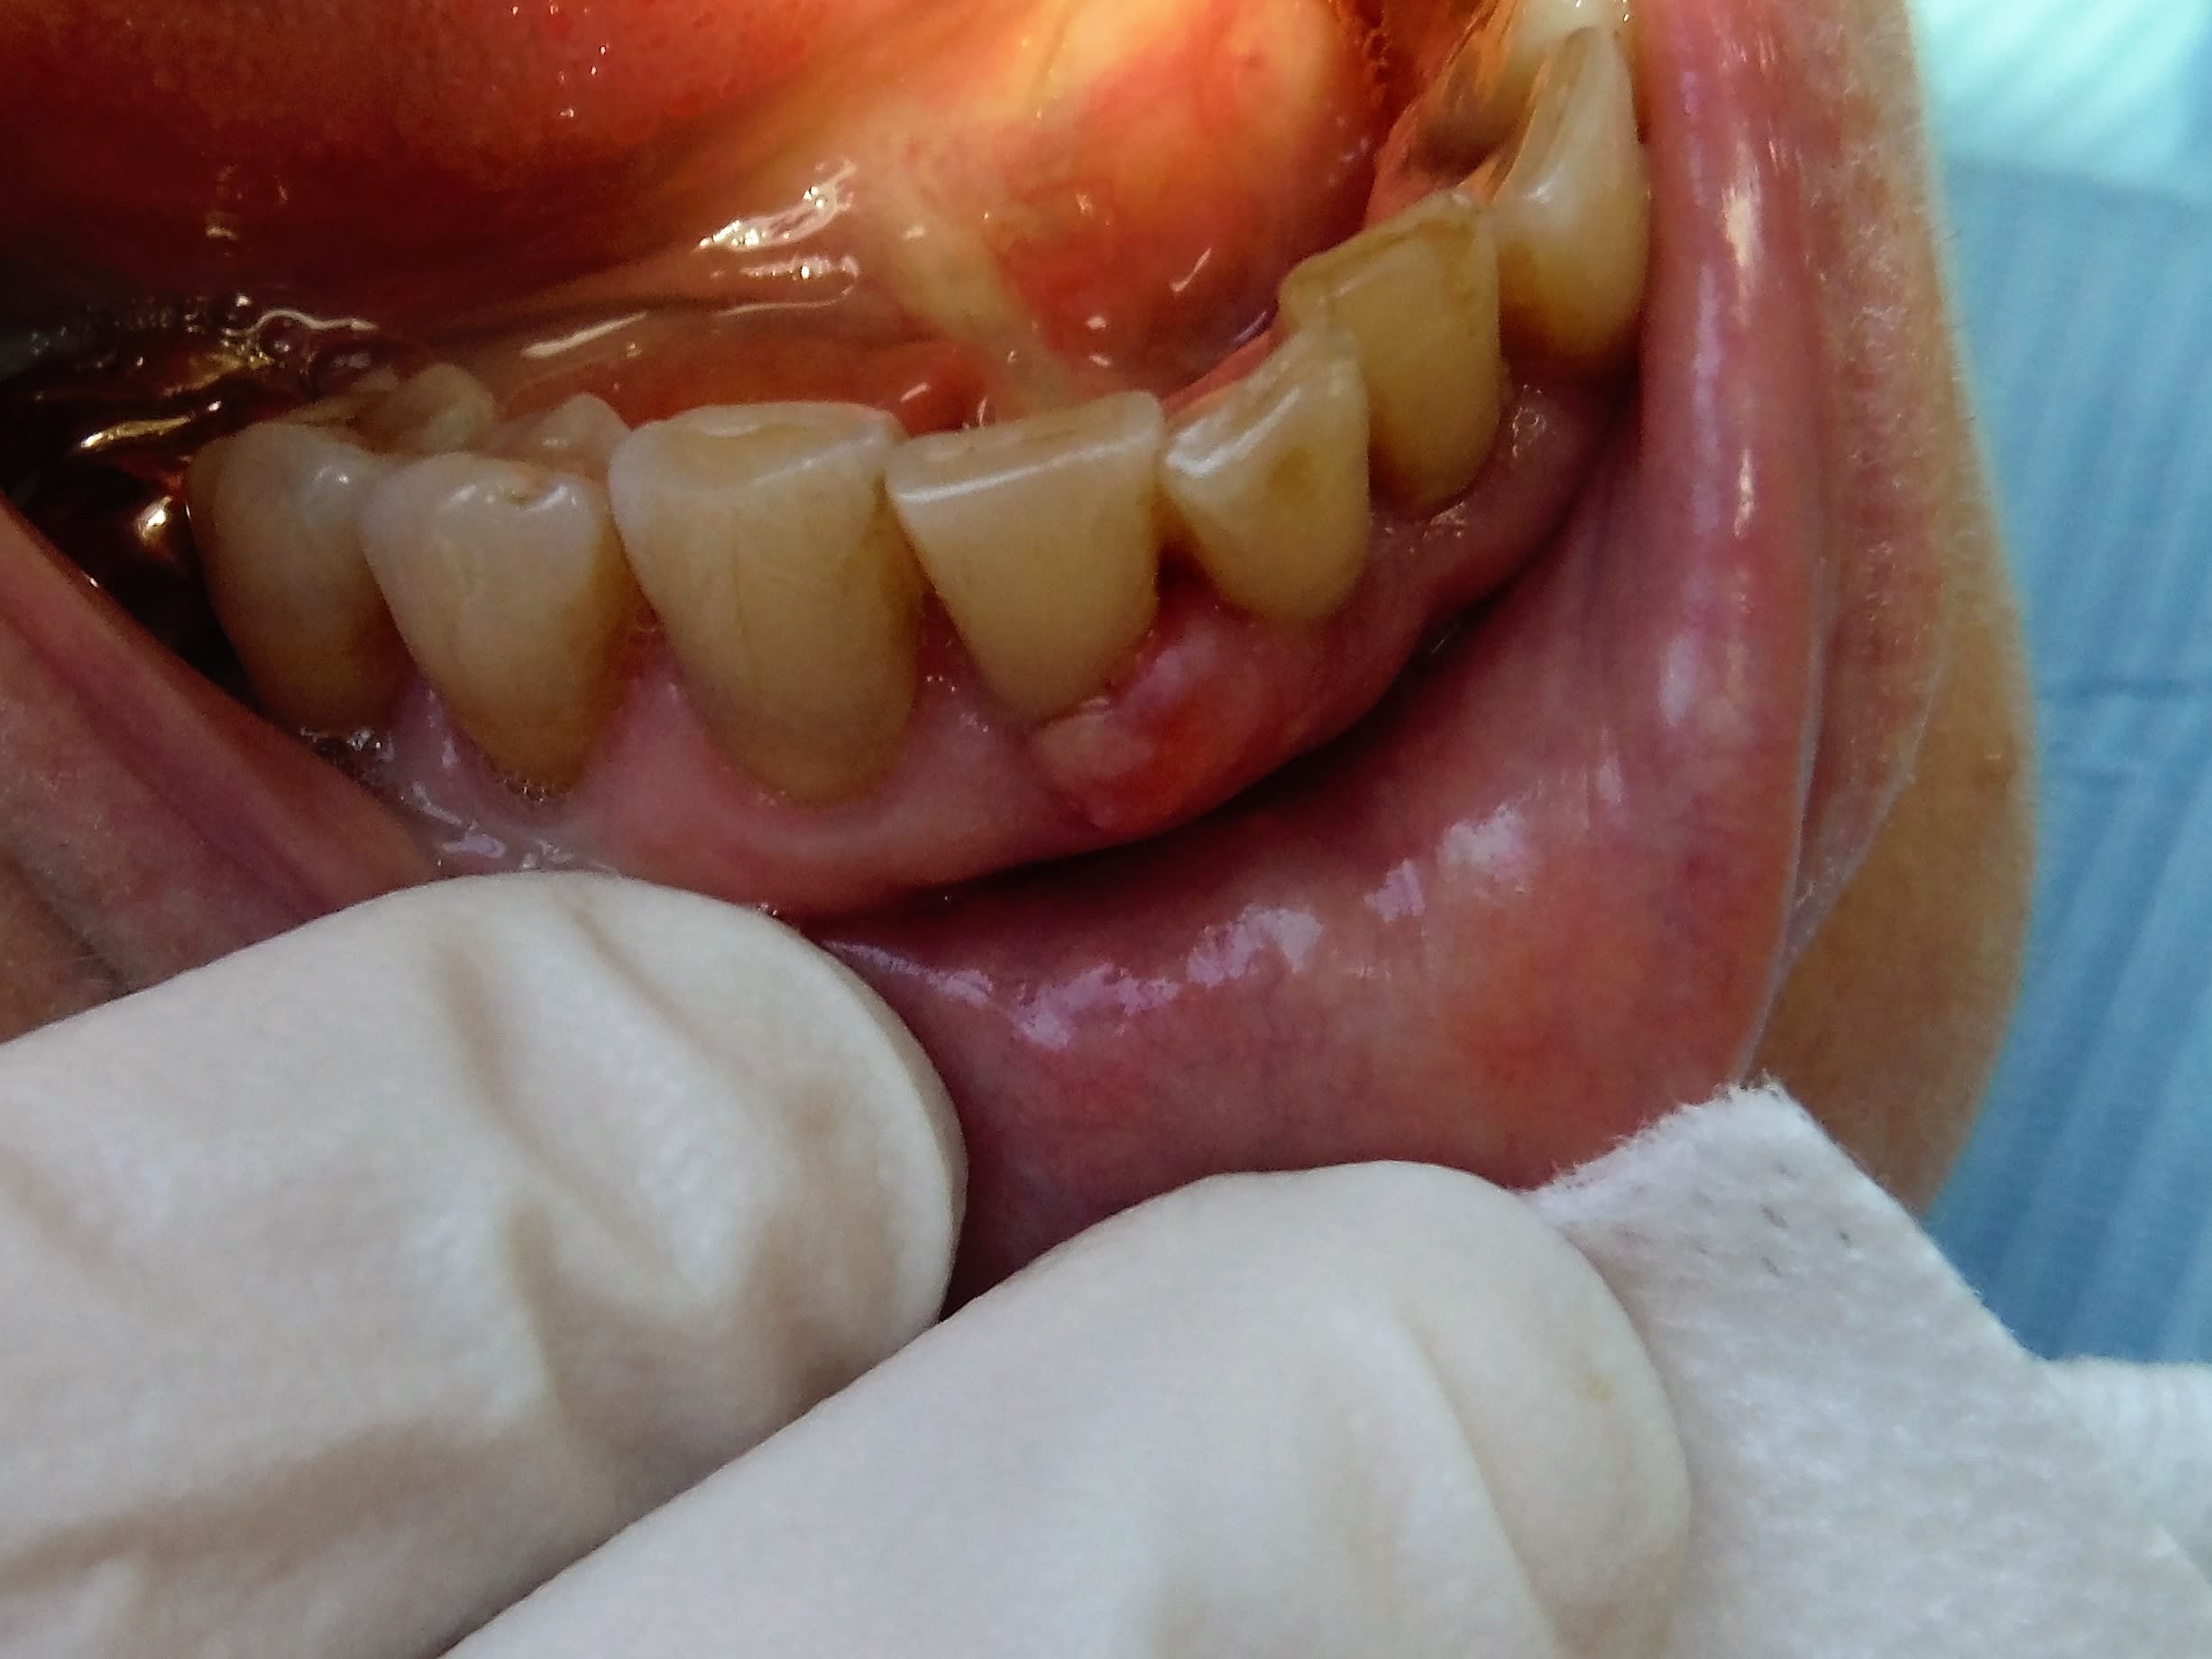

Pour les pigmentations ethniques, cela vient principalement de la mère... les asias ont une tache bleue en bas du dos, pour les blacks ce genre de tatouage sur la gencive... mais c'est quasi toujours lié aux origines de la mère.

Ne pas oublier, tout ce qui est tatoué et à moi.